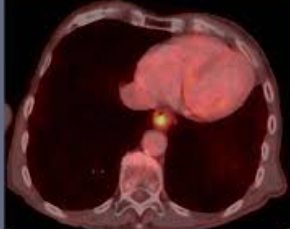

1. 상부 내시경 검사: 이 절차는 식도와 위를 검사하기 위해 조명과 카메라(내시경)가 장착된 얇고 유연한 튜브를 목 아래로 삽입하는 절차입니다. 식도의 염증, 궤양 또는 기타 변화를 식별할 수 있습니다.

3. 외래산(pH) 탐침 검사: 이 검사는 장치를 사용하여 위산이 식도로 역류하는 시기와 기간을 식별합니다. 위산 역류를 확인하기 위해 장치를 식도에 삽입합니다.